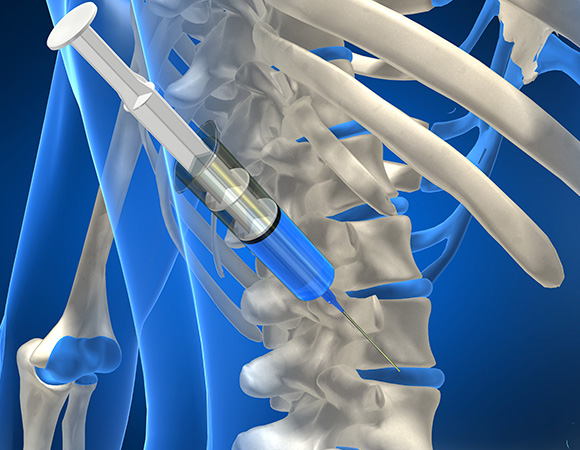

증식치료 (prolo therapy)

무릎 주변의 약해진 힘줄 인대의 강화

주사치료

연골을 재생하거나 보호하는 약제를 관절내에 주입